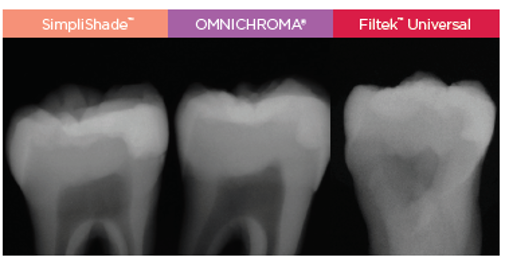

Uitstekende radiopaciteit

SimpliShade heeft een radiopaciteit van 300% AI.

Röntgen foto van menselijke tand met Klasse II restauratie. Data opvraagbaar